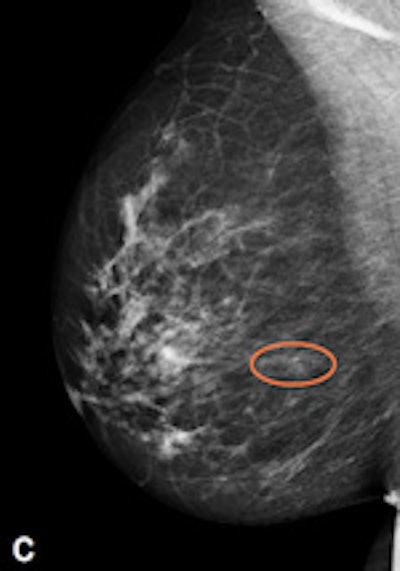

| Example of a subtle finding in a right-sided mediolateral oblique view, which was only reported by radiologists when using premium view (PV). A: Digitized prior. B: Tissue equalization (TE) processed image. C: PV processed image with the annotation. D: The resulting image of subtracting TE from PV. E: Thresholded version of D. White areas indicate that pixels in the PV image have relatively higher intensity than the related pixels in the TE image, whereas black areas indicate the opposite. In PV images, low-frequency trends are suppressed (no noticeable signal decrease in the breast edge in PV compared with TE), whereas higher-frequency structures are emphasized (e.g., glandular structures). All images courtesy of Wouter Veldkamp, PhD, Leiden University Medical Center. |

The cases were acquired using the Senographe Essential digital mammography system (GE Healthcare). Tissue equalization is a standard GE application that corrects for low-frequency variations resulting from under- and overpenetration of x-rays. As a result, the image dynamic range is reduced, enabling improved soft-copy image display.

The local contrast optimization, premium view, has been designed to improve the quality of the information presented to the radiologist for diagnosis and also the reading speed by optimizing the local contrast in breast structures. In premium view, low-frequency structures are obtained from the original image by low-pass filtering. High-frequency structures are obtained by subtracting the low-pass filtered image from the original image. The low- and high-frequency images are both processed and weighted individually, then added together. The resulting image exhibits reduced contrast between different tissue types but enhanced contrast of small-scale anatomical architecture.

Another example of a finding in a left-sided craniocaudal view that was reported clearly more often by radiologists when using premium view (PV). A: Tissue equalization (TE) processed image. B: PV processed image with the annotation. C: Similar to image above, the resulting image of subtracting TE from PV. D: The thresholded version of C.For all six radiologists, perceived case suspiciousness -- defined as the highest probability of malignancy of all radiologist findings -- was higher using premium view optimization.